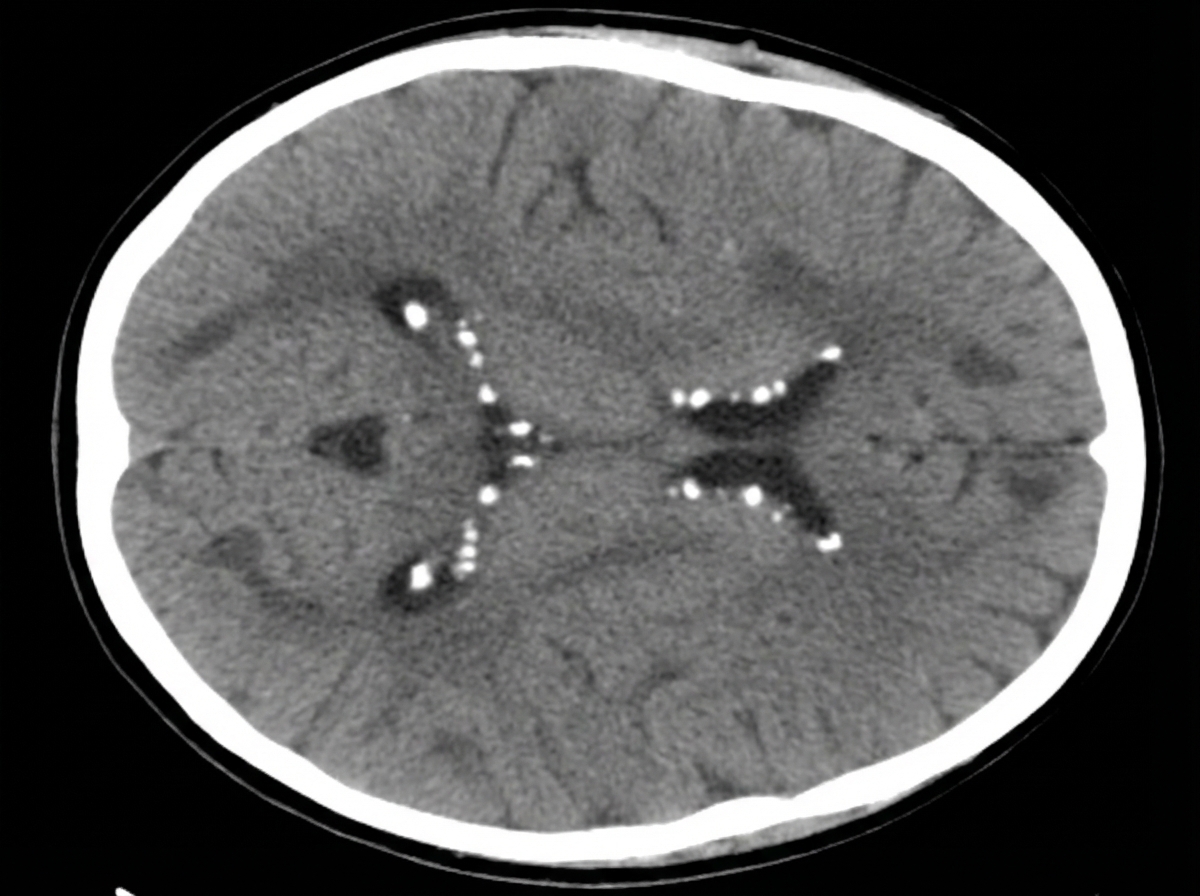

A 12-year-old boy presents with seizures. His mother reports multiple previous hospitalizations for difficult-to-control seizures. A CT scan was performed. What is the diagnosis?

Explanation: ***Tuberous sclerosis*** - Characterized by **subependymal calcified nodules** and **cortical tubers** on CT, which are pathognomonic findings in children with refractory seizures. - Classic presentation includes **difficult-to-control seizures** in childhood, often associated with **developmental delay** and **autism spectrum disorders**. *Sturge Weber Syndrome* - CT typically shows **pial angiomatosis** with **gyriform calcifications** in the occipital and parietal regions, not subependymal nodules. - Associated with **port-wine stain** facial birthmark and **glaucoma**, which are not mentioned in this case. *Neurofibromatosis* - CT findings include **neurofibromas** and **optic gliomas**, not the calcified nodules seen in tuberous sclerosis. - Typically presents with **café-au-lait spots** and **neurofibromas** rather than primarily seizure disorders. *Von Hippel Lindau Syndrome* - CT shows **cerebellar hemangioblastomas** and **retinal angiomas**, not cortical tubers or subependymal nodules. - Primarily affects **young adults** rather than children and rarely presents with seizures as the main symptom.